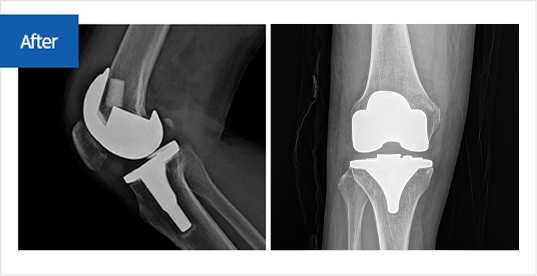

수술 전후 무릎관절 변화

뼈가 맞닿아 통증을 유발하던 공간이 확보되어 통증이 완화되며, 본래의 관절 운동 기능이 회복됨

정상관절 img before img after img